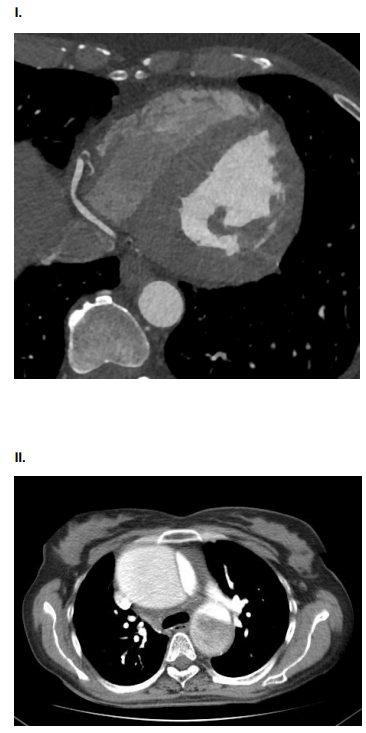

AMV, 75 anos, tabagista, com queixa de dor torácica

súbito, do tipo lancinante. Ao exame físico: Regular estado

geral. ACV: RCR em 2T, pulsos radiais assimétricos. PA:

150x80 mmHg. FC 110. Sat O2 90%. Solicitado ECG e

Tomografia de Tórax e Abdome com contraste.

Assinale a alternativa que contenha o achado compatível com o quadro clínico da paciente.